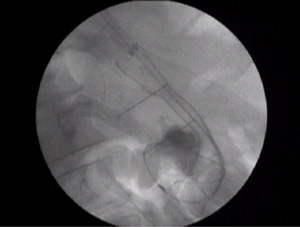

MR AS,male /55 yr was operated for distal gastrectomy for carcinoma stomach 7yrs back.He had recurrence 12 months back when he got total gastrectomy with roux-en-y esophageal-jejunal anastomosis.The jejunum was made into a J-shaped using staplers and anastomosed.He underwent chemotherapy.Recently,patient had absolute dysphagia to solids and liquids he could take inadequately.His PET scan confirmed recurrence at the site of anastomosis.

His gastroscopy was done and the scope could not be negotiated across tha anstomosis.The wire could not be passed under fluoroscopy for dilatation with another gastroenterologist .

I could pass a wire and dilate the esophago-jejunal anastomosis with placement of a covered metallic self expandeble stent for palliation of dysphagia with half of the covered stent in the j-shaped jejunum and half proximally.

The covered stent will serve to maintain nutrition in this advanced disease .